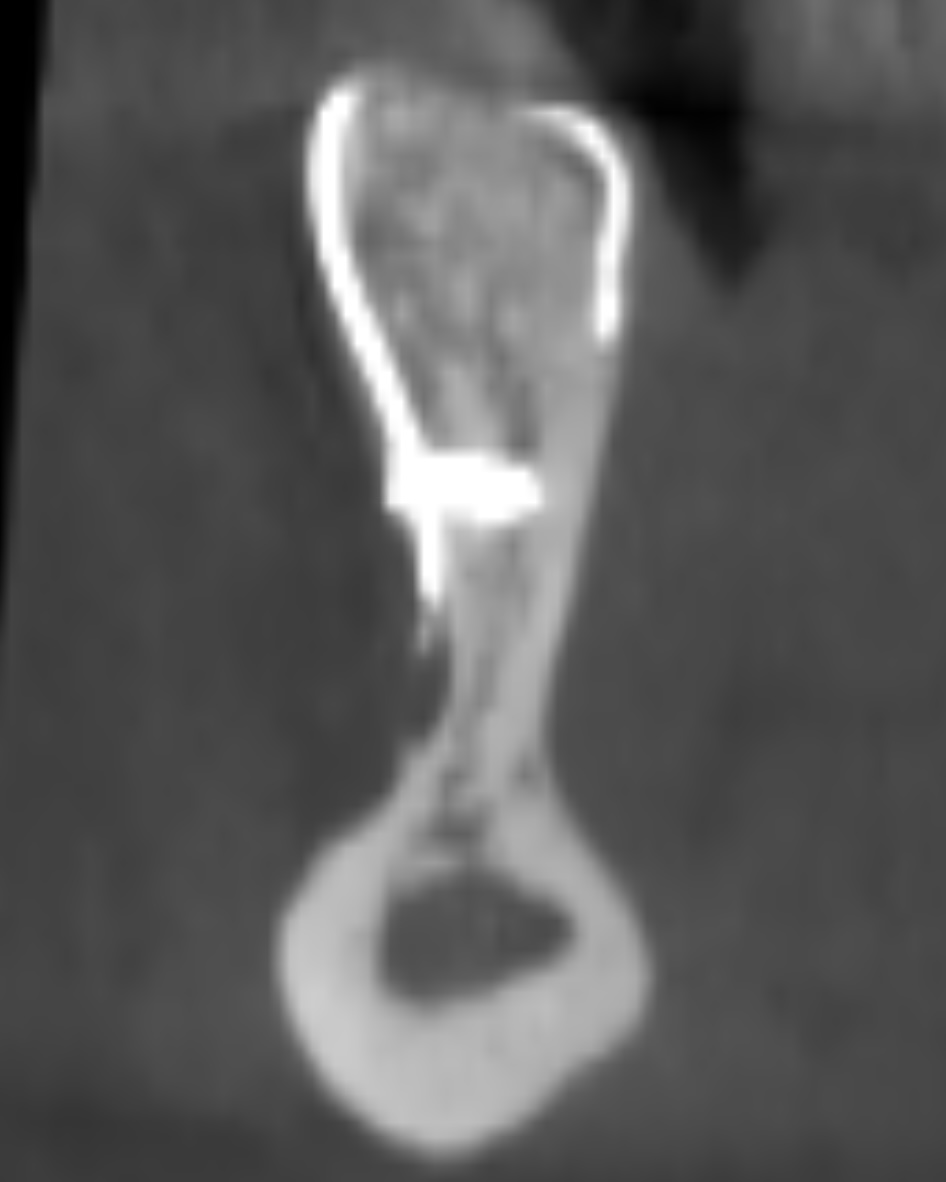

La visualizzazione della CBCT (Figure 2a-b) permette di valutare tridimensionalmente l’atrofia riscontrata durante l’esame clinico. Le immagini ricavate dalla rx evidenziano come l’atrofia sia stata sottostimata rispetto alle aspettative, in quanto la sezione di mandibola mostra un aspetto a lama di coltello con un importante sottosquadro linguale. Prima di poter procedere al posizionamento implantare risulta quindi necessario intervenire con la rigenerazione del volume osseo corretto. Viene pertanto proposta alla paziente una chirurgia rigenerativa realizzata mediante l’ausilio di una griglia customizzata in titanio, realizzata sulla base della ricostruzione tridimensionale ricavata dalla Cone Beam.

L’intervento inizia con un’incisione crestale sulla sella edentula, proseguita in direzione mesiale intrasulculare all’elemento 4.3 e completata con un’incisione di rilascio mesiale in modo da permettere la chiara visualizzazione del sito. Si esegue la scheletrizzazione del corpo mandibolare andando a identificare e proteggere il nervo mentoniero, che alla sua fuoriuscita dal foro omonimo presenta aspetto bifido (Figura 4). Viene infine eseguito il rilascio dei lembi mediante incisioni periostali affinché questi possano essere successivamente riposizionati e suturati passivamente.